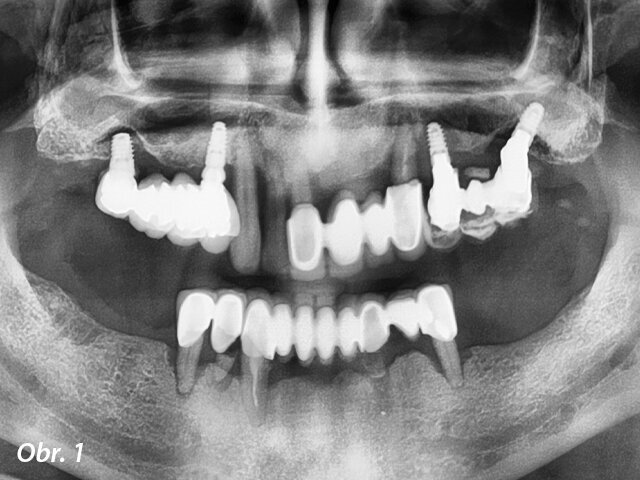

Na kliniku se dostavil 66letý pacient, klasifikovaný jako ASA II, stěžující si na bolest, mobilitu zubů a diskomfort v levé části horní čelisti. Klinické vyšetření odhalilo pokročilé onemocnění parodontu stupně C a fáze IV podle nové klasifikace periodontálních onemocnění. Bylo zjištěno spontánní krvácení, hnisání a celkově vysoký stupeň zánětu.10 Pacient měl metalokeramické korunky v dolní čelisti a tři různé můstky v horní čelisti. Všechny byly extrémně mobilní, a to mezi stupněm II a III. Panoramatický RTG snímek ukázal difúzní a pokročilý stupeň resorpce kosti zasahující ke všem zbývajícím zubům (obr. 1). V horní čelisti byly čtyři implantáty, dva z nich s hlubokými kostními defekty kolem fixtur. CBCT sken potvrdil diagnózu zubů stanovenou pomocí panoramatického RTG snímku a prokázal velký hluboký kostní defekt v rozsahu od špičáku až za první levý premolár a velmi malou výšku kosti pod levou i pravou stranou dna sinu (obr. 2). Levá strana sinu vypadala téměř celá zaplněná zánětlivou hyperplazickou tkání.

Panoramatický RTG snímek zubů pacienta. Je vidět pokročilá resorpce kosti.